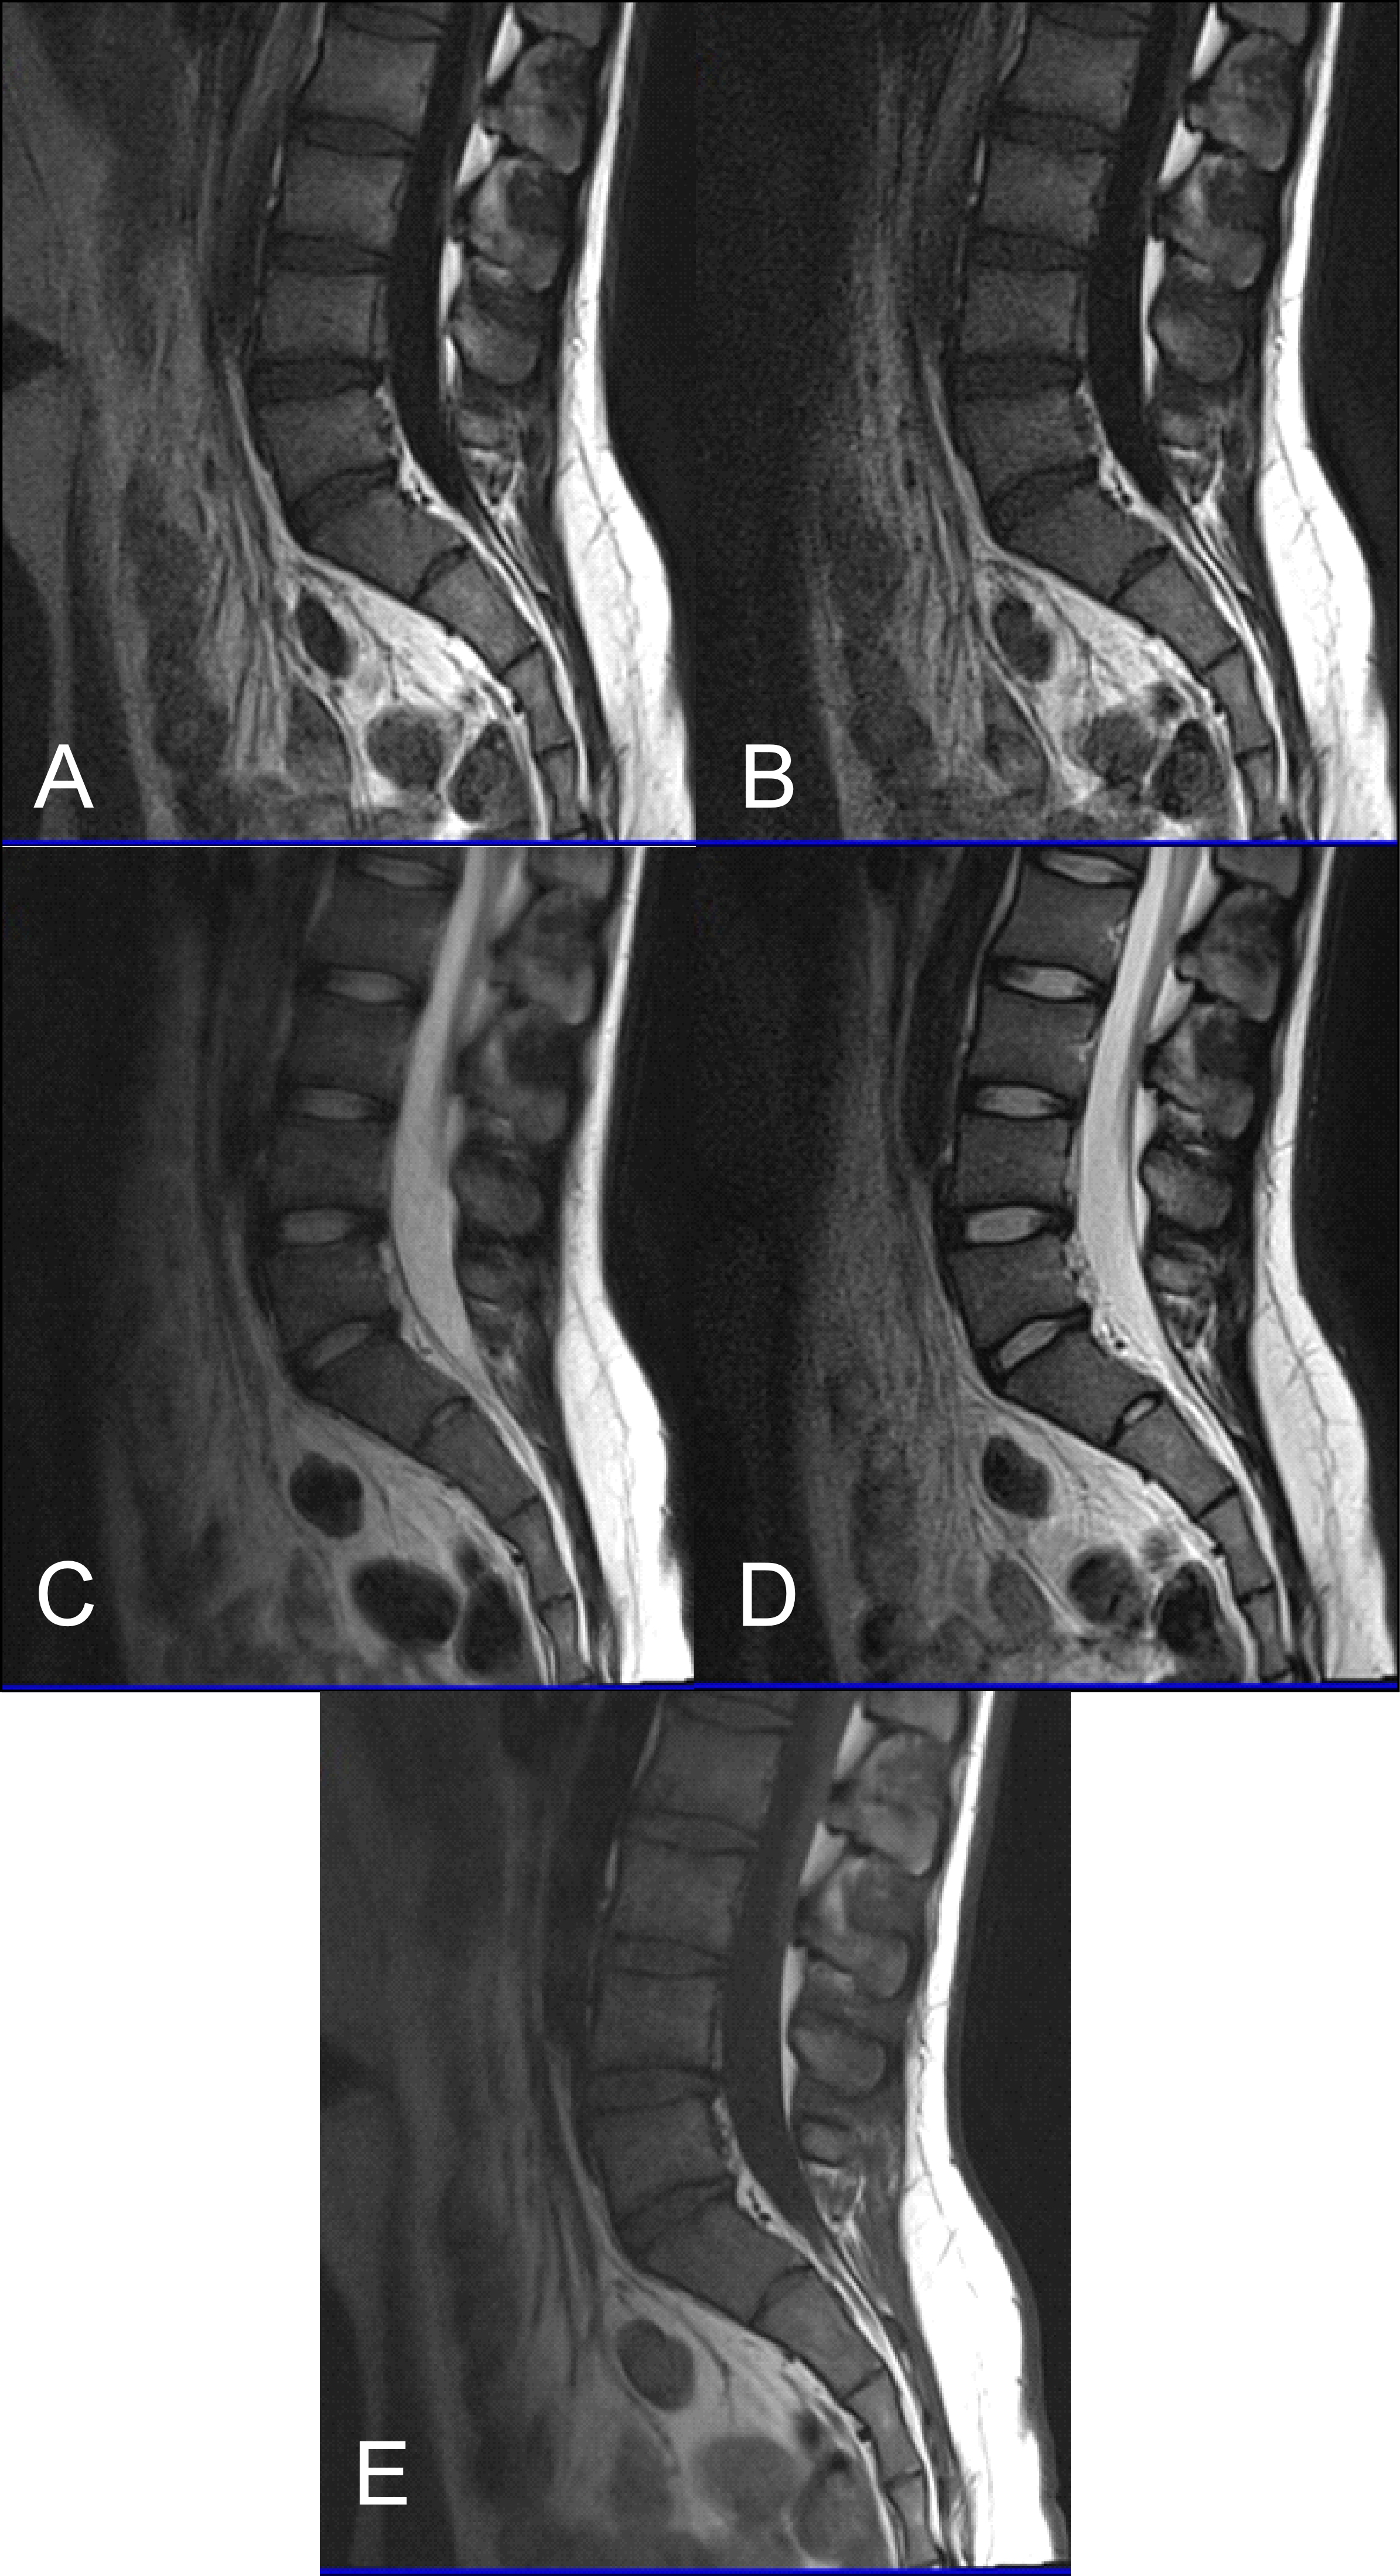

The results obtained from the quantitative analysis of this study showed that the SNR and CNR results were significantly greater for T1W-FLAIR BLADE. More specifically, T1W-FLAIR BLADE sequence achieved better CSF nulling and better contrast between spongy bone and intervertebral disc as well as between spongy bone and intervertebral disc with CSF (Figure 2). A study by Alibek et al., has also demonstrated the superiority in image contrast of T1W-FLAIR images showing that they achieve better lesion to background and grey to white matter CNR [19]. The inherent restrictions of parallel imaging, i.e., reduction of SNR and increased possibility for reconstruction artifacts, were confirmed in our findings where the images without parallel imaging had better SNR (Figure 3).

As stated earlier, sagittal T1 weighted images play an integral role in the MR imaging of the L-spine. One of the reasons is that they provide great information about anatomical structures. In order to assess the importance of the BLADE sequence compared to a TSE, both a qualitative and quantitative analysis were performed by evaluating contrast in between anatomical structures and the SNR, CNR and ReCon measurement respectively [18]. Although T1W-TSE is a faster sequence, T1W-FLAIR BLADE scored better in quantitative and qualitative analyses. Pathologies and abnormalities were better visualized in the latter one. Furthermore, in T1W-FLAIR BLADE there was improved image contrast as well as greater depiction of anatomical structures and either degeneration or metastatic lesions. Both the quantitative and qualitative analysis showed that T1W-FLAIR BLADE achieved better results than T1W-TSE. In addition to that, T1W-FLAIR BLADE images without parallel imaging were found to have better quality than the T1W-FLAIR BLADE images with parallel imaging. Although they both eliminated motion artifacts, the images without parallel imaging have better SNR as well as better contrast between tissues (Figure 3). Moreover, a study showed that T1W-FLAIR images can successfully eliminate chemical shift artifacts compared to T1W-TSE due to greater receiver bandwidth [8]. This statement was confirmed by our findings (Figure 4).

T1W-FLAIR BLADE also had higher values in all the relative contrast measurements. T1W-FLAIR BLADE showed better results when comparing CSF with spongy bone, CSF with intervertebral disc and intervertebral disc with spongy bone. These results from the quantitative analysis meant better conspicuity between the following anatomical structures: intervertebral disc-CSF, intervertebral disc-spinal cord, vertebral body-CSF and spinal cord-CSF. Both radiologists found that T1W-FLAIR images achieved better CSF nulling compared to T1W-TSE. It was also found that T1W-FLAIR BLADE was significantly superior to T1W-TSE when reviewing the contrast at the spinal cord and cauda equina interface, demonstrating substantial inter-observer agreement. Due to CSF nulling that is achieved in FLAIR sequences, T1W-FLAIR sequence is a very useful tool to distinguish cysts within the spinal cord, tumors and demyelinating disease. Another study showed that T1W-FLAIR images had also a higher CNR over T1W-TSE images in 16 metastatic lesions in the vertebrae, which helped diagnose the extent of the lesion in the spinal cord. Moreover, the findings of this study are in line with the results of other studies, which show that the T1W-FLAIR sequence could be more beneficial for L-spine imaging than T1W-TSE, due to CSF nulling, higher image contrast and definition of anatomical structures, degeneration, or metastatic lesions (Figure 5) [11]. The results of our study also support the above, i.e., T1W-FLAIR BLADE being superior to T1W-TSE for the aforementioned reasons.